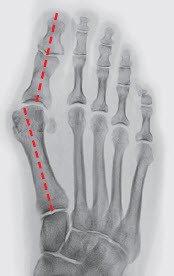

Durch diese Fehlstellung verliert die Grosszehe einen Teil ihrer wichtigen Stützfunktion und der benachbarte zweite Mittelfussknochen (Abbildung 2) wird chronisch überbelastet. Die Überlastung zeigt sich in der häufig beobachteten, schmerzhaften Hornhautverdickung unterhalb des zweiten (oft auch dritten) Mittelfussköpfchens. Die dort stark strapazierten Bänder und die Gelenkkapsel der zweiten (und dritten) Zehe können einreissen, sodass die Zehe keinen Halt mehr hat und sich eine Hammerzehe bildet (Abbildung 3).

Ziel der Chirurgie ist die möglichst exakte Wiederherstellung einer normalen Anatomie, wie sie vor dem Auftreten der Deformität bestanden hat. Der schräg stehende Mittelfussknochen, der nach innen drückt, muss also aufgerichtet und in der korrekten Stellung stabilisiert werden. Die Grosszehe steht dann wieder gerade auf dem Mittelfussknochen und entfaltet ihre volle Stützfunktion, was die Überlastungsschmerzen an der Fusssohle zum Verschwinden bringt. Das bei uns am häufigsten angewandte Operationsverfahren ist die sogenannte «Scarf»-Osteotomie, die hier dargestellt wird. Diese Korrektur erfolgt durch einen Knochenschnitt (Osteotomie), der mit zwei bis drei kleinen Schrauben in der korrekten Stellung bis zur Heilung (sechs bis acht Wochen) fixiert wird. Die später funktionslos gewordenen Schrauben spürt man nicht, sie müssen nur ausnahmsweise entfernt werden.